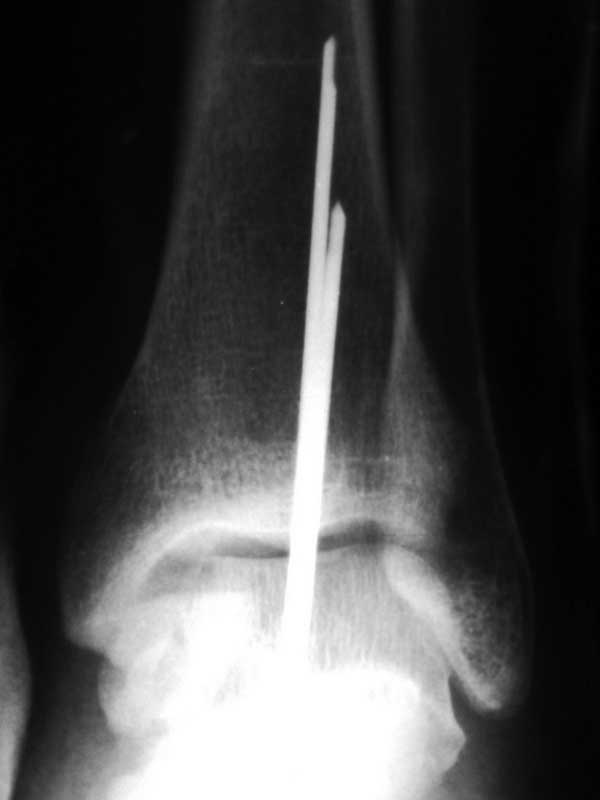

[Ortho] Переломовывих таранной кости

> п÷я─я▐п╪п╟я▐ п©я─п╬п╣п╨я├п╦я▐